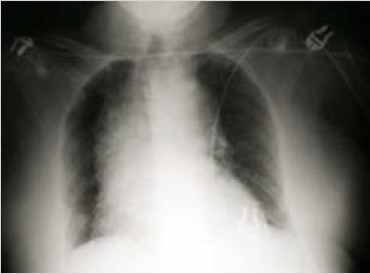

02.- Un varón de 68 años, con antecedentes de hipertensión arterial mal controlada, acude al Servicio de Urgencias con un dolor centrotorácico brusco y desgarrador, irradiado a espalda. La presión arterial es 200/110 mmHg. En la radiografía de tórax se aprecia lo que se muestra en la imagen adjunta.

Ante este cuadro clínico, lo primero que deberías plantearte es una disección aórtica. Recuerda que, en un síndrome aórtico agudo, existe asociación con HTA aproximadamente en un 75% de los casos. De hecho, en este caso enfatizan el mal control de su hipertensión. Desde el punto de vista exploratorio, resulta muy típica la asimetría de los pulsos, que en este caso no nos mencionan.

La imagen clínica acompañante nos muestra un claro ensanchamiento del mediastino. Éste es el hallazgo radiológico más frecuente cuando se realiza una radiografía de tórax en este tipo de pacientes. A veces, también podríamos encontrarnos un derrame pleural, habitualmente izquierdo, por extravasación de sangre. No olvides que, hasta en un 20% de los casos, la radiografía torácica puede ser totalmente normal.

Tal como dice la respuesta D, deberíamos realizar una TC con contraste y avisar al cirujano cardíaco, ya que lo más probable es que se trate de una disección de aorta ascendente (tipo A de Stanford), cuyo tratamiento es quirúrgico. En caso de realizarse una TC, podríamos encontrar una imagen como la que se muestra a continuación. Presta atención a las flechas, que señalan la falsa luz en la que se muestra la disección. Recuerda que si la disección es tipo B, el tratamiento es conservador.